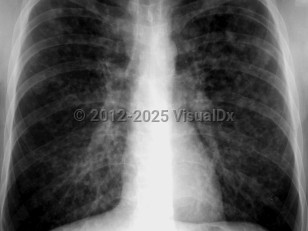

Pulmonary edema

Pulmonary emphysemaPulmonary emphysema